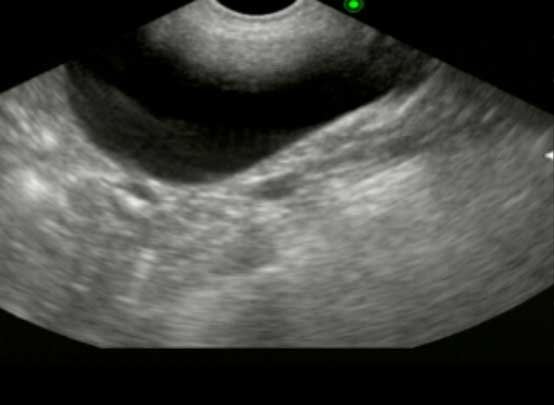

超音波検査

腎臓や膀胱の内部構造を確認します。腎臓においては形態や構造の変化、血流の評価を、膀胱においては壁の厚さや不整、内部の結石や血餅などの評価を行います。その他にも、尿管や尿道、雌では子宮や卵巣、雄は前立腺の評価にも有用です。

超音波腎臓

超音波膀胱